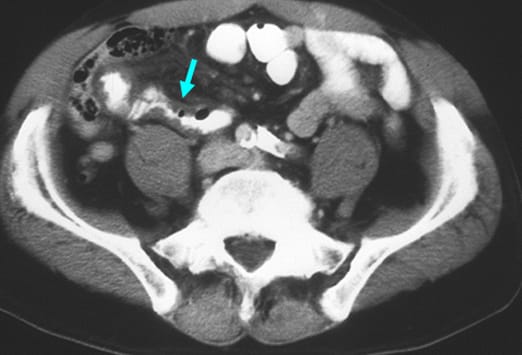

Eine atypische Appendizitis (siehe Abbildung) stellt eine diagnostische Herausforderung dar. Dieser 54-jährige Mann hatte seit 2 Tagen periumbilicale Schmerzen, eine Leukozytose und eine Abwehrspannung im Mittelbauch. Die CT-Untersuchung ergab den Befund einer Malrotation des Kolons mit einer Appendizitis (Pfeil) im Bereich des linken Oberbauchs. Man beachte den perityphlitischen Abszess. Trotzdem verursacht eine Appendizitis typischerweise Schmerzen im Bereich des rechten Unterbauches. Dies ist wichtig bei der raschen Erhebung einer Differentialdiagnose.